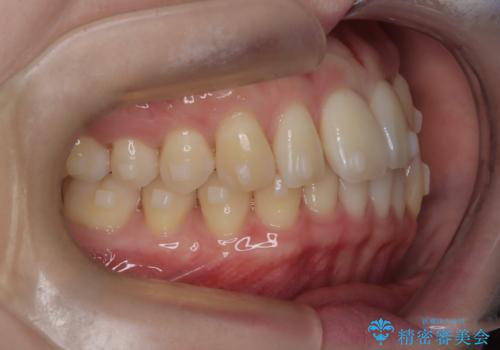

- 左上2の反対咬合(交叉咬合)をインビザラインを用いて治療しました。反対咬合は、歯列の不正咬合の一つであり、上の歯が下の歯よりも内側に位置する状態です。反対咬合は咀嚼や発音に影響を与えることがあります。

左上2の反対咬合をインビザラインで治療する際に、IPR(Interproximal Reduction)を行いました。 IPRとは、隣接する歯の間のエナメル質をわずかに削る手法で、歯の幅を減少させることによって歯列を整える技術です。